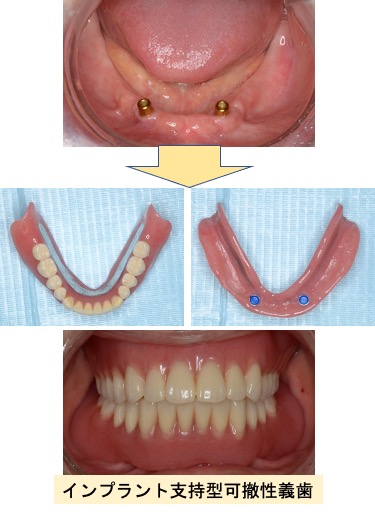

入れ歯(有床義歯)治療

むし歯や歯周病などが原因で、歯を失った場合の治療です。たくさん歯が残っている場合には、ブリッジによる治療が機能性・審美性に優れ、違和感も少ないのですが、ブリッジの支えになる歯が丈夫でなかったり、失った歯の本数が多い場合には入れ歯による治療が適応になります。入れ歯は材質やデザインによって見た目や装着感が大きく異なります。個々の患者さんに合わせた入れ歯を作製いたします。